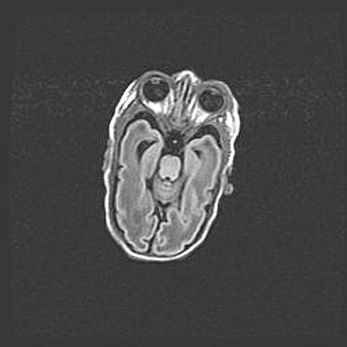

Сообщающаяся гидроцефалия. Кистозная энцефаломаляция головного мозга.

Возраст: 3 месяца 4 дня

Вес: 3100 г

Пол: женский

Окружность головы: 34 см

Срок гестации: 31 неделя

Кистозная энцефаломаляция головного мозга - одна из форм поражения головного мозга в детском возрасте. Характеризуется возникновением множественных и распространённых кист в коре, белом веществе и подкорковых образованиях головного мозга у плодов, новорождённых и детей раннего возраста. Развитие кистозной энцефаломаляции связано с внутриутробной асфиксией и гипотонией, родовой травмой, тромбозом синусов, пороками развития сосудов, инфекциями, сепсисом и другими причинами. Наиболее значимые инфекционные агенты: вирусы простого герпеса, цитомегалии, краснухи, токсоплазмы, энтеробактерии, золотистый стафилококк и другие.